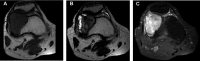

We provide an overview of imaging, histopathology, genetics, and multidisciplinary treatment of giant cell tumor of bone (GCTB), an intermediate, locally aggressive but rarely metastasizing tumor. Overexpression of receptor activator of nuclear factor κB ligand (RANKL) by mononuclear neoplastic stromal cells promotes recruitment of numerous reactive multinucleated giant cells. Conventional radiographs show a typical eccentric lytic lesion, mostly located in the meta-epiphyseal area of long bones. GCTB may also arise in the axial skeleton and very occasionally in the small bones of hands and feet. Magnetic resonance imaging is necessary to evaluate the extent of GCTB within bone and surrounding soft tissues to plan a surgical approach. Curettage with local adjuvants is the preferred treatment. Recurrence rates after curettage with phenol and polymethylmethacrylate (PMMA; 8%-27%) or cryosurgery and PMMA (0%-20%) are comparable. Resection is indicated when joint salvage is not feasible (e.g., intra-articular fracture with soft tissue component). Denosumab (RANKL inhibitor) blocks and bisphosphonates inhibit GCTB-derived osteoclast resorption. With bisphosphonates, stabilization of local and metastatic disease has been reported, although level of evidence was low. Denosumab has been studied to a larger extent and seems to be effective in facilitating intralesional surgery after therapy. Denosumab was recently registered for unresectable disease. Moderate-dose radiotherapy (40-55 Gy) is restricted to rare cases in which surgery would lead to unacceptable morbidity and RANKL inhibitors are contraindicated or unavailable.